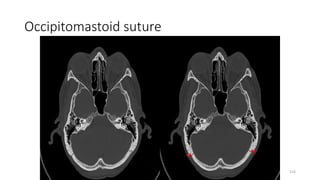

LEVEL-8

OCCIPITO MASTOID SUTURE